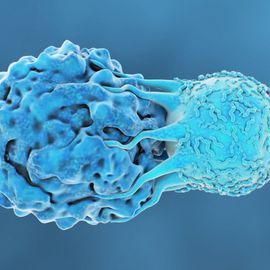

抗癌治疗

这个页面提供了教育资源、事件、新闻和产品相关抗癌疗法。内容将涵盖方面,从化疗和放射治疗,细胞治疗和癌症疫苗。

癌症免疫学

这个页面提供了教育资源、事件、新闻和产品相关的癌症免疫学。内容将涵盖从肿瘤免疫微环境和免疫监视方面,癌症免疫疗法和疫苗。